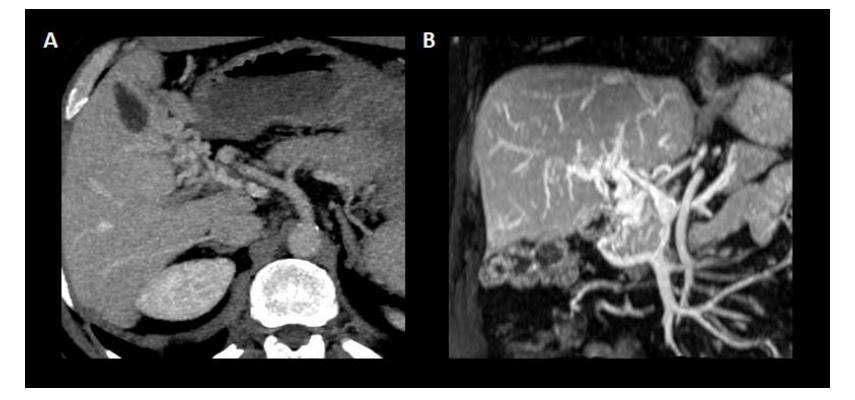

图4.门静脉海绵样变。(A)显示门静脉主干被起源于门静脉血管的门静脉侧支取代的轴位平面。(B)门静脉的冠状面及其海绵样变与构成门静脉侧支的新血管的缠绕。